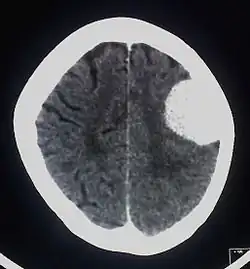

Brain tumor

The investigations completed at the Eberhard Karls University of Tuebingen in 2003 by Alfred Czarnetzki, Carsten M. Pusch and Erwin Schwaderer, showed that the owner of the skull suffered from a meningioma, which is an arachnoid tumor.[9] Meningiomas are a diverse set of tumors that arise from the meninges, which is the membranous layers surrounding the central nervous system.[10]

The slow-growing tumor had a size of 51 mm × 43 mm × 25 mm and a volume of 29 ml (1 imp fl oz; 1 US fl oz). It is believed that this tumor may have caused headaches. It is also possible that no neurological deficiencies were suffered, due to the slow growing nature of meningiomas.[9] Whether the tumor should be considered the cause of death cannot be determined from the remains. Having the rest of the skeleton would be necessary for further investigation into a possible cause of death. Meningiomas are very rare with roughly 2 out of 100,000 causing symptoms, so finding evidence of one in such ancient remains is a very exciting discovery.[11] It is the earliest evidence of a meningioma tumor on record.